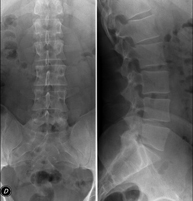

Tècnica que usa els raigs X a través de la qual s'obtenen imatges de la columna dorsal per al seu estudi. Indicacions: traumatisme, mal d'esquena. - RX Columna lumbar

Tècnica que usa els raigs X a través de la qual s'obtenen imatges de la columna lumbar per al seu estudi. Indicacions: ciàtica, traumatisme, dolor lumbar. - RX Sacre-còccix

Tècnica que usa els raigs X a través de la qual s'obtenen imatges del sacre i del còccix per al seu estudi. Indicacions: traumatisme, dolor sacre o coccigi. - Telerradiologia columna

Tècnica que usa els raigs X a través de la qual s'obtenen imatges de tota la columna vertebral per al seu estudi, amb la valoració especialment de la presència d'escoliosi i dismetries pèlviques.